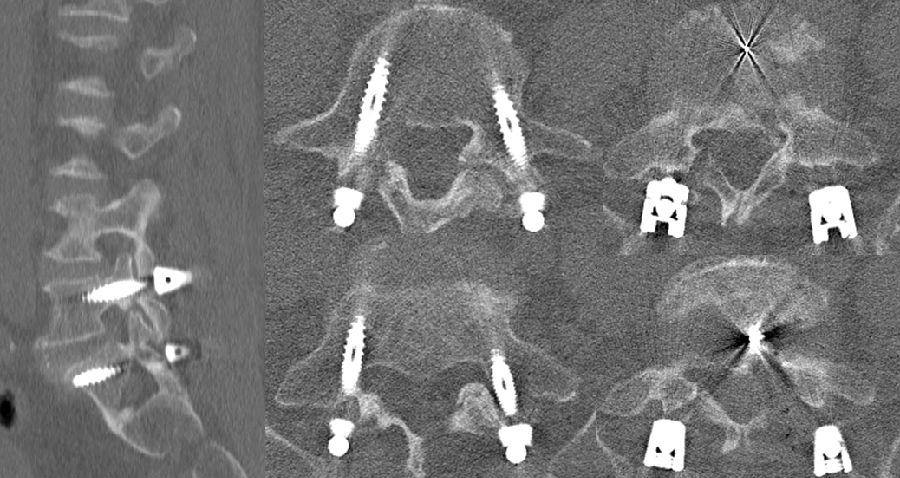

八、医源性不稳定(0.88%)

发生率0.6%,明显低于开放式手术,小关节突关节损伤是主要原因。上腰椎(L1~L3)病变、存在狭窄椎板和脊柱矢状面失衡的患者减压过程几率更高。

病例(关节突损伤)

男,52岁。

主诉:腰痛20余年,双下肢疼痛10余年,加重4天。

查体:双侧直腿抬高试验及加强试验(-),双侧膝腱反射及跟腱反射未引出,Babinski征(-)。

思考及建议

使用磨钻从棘突基底部与上椎板下缘交界处切开

术前CT测量关节突切除范围

L3-4及以上节段,对侧入路切除椎间盘